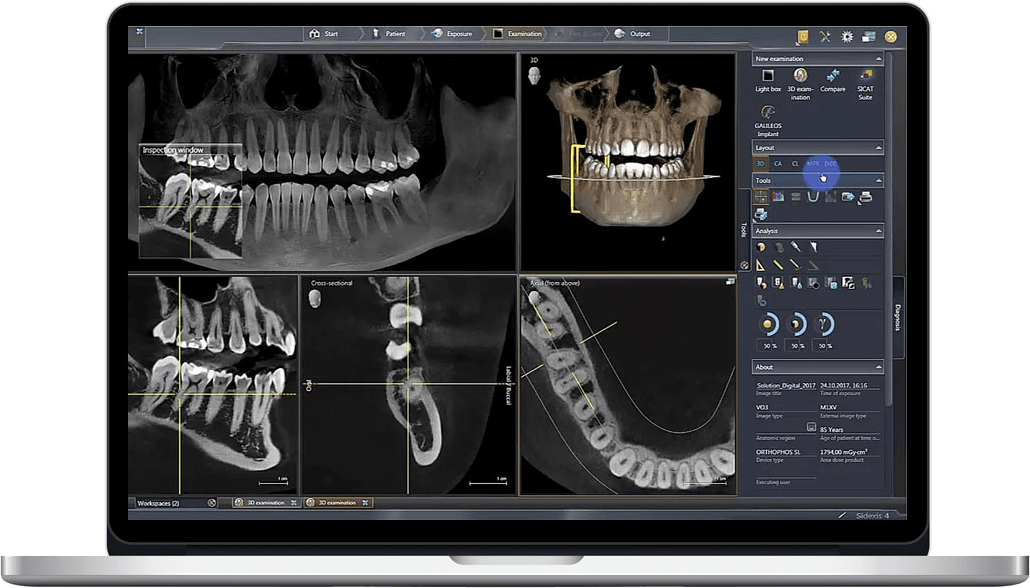

CBCT (Cone Beam Computed Tomography) has evolved beyond diagnostic imaging to become the structural backbone of integrated digital workflows. In 2026, its strategic integration enables:

- Anatomical Contextualization: Merging surface scans (intraoral/optical) with volumetric CBCT data creates true 3D anatomical models (e.g., cortical bone thickness, nerve canal mapping)

- Dynamic Treatment Simulation: Real-time biomechanical stress analysis for implant positioning based on bone density gradients derived from Hounsfield Unit (HU) calibrated CBCT

- Automated Pathology Detection: AI-driven segmentation of CBCT data identifies periapical lesions, cysts, and sinus anomalies before restorative design begins

CBCT Integration in Chairside/Lab Workflows: Technical Implementation

| Design Phase | Basic implant planning only; no integration with crown/bridge design | Simultaneous visualization of CBCT bone data + IOS surface scan in single CAD environment |